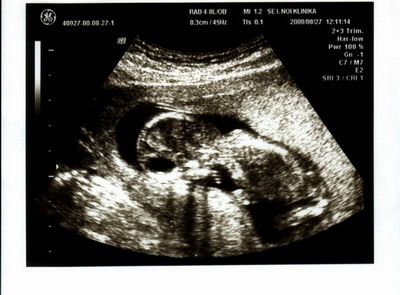

Megpróbálok feltenni képet a múltkori uh-ról. Nem vmi naprakész, de amíg nincs más és izgulok, hogy minden rendben van-e, ezt szoktam nézegetni. :D

Szép napot! Kép

ggica nagyon helyes a babód uh-képe.... :lol:

Gica: Nagyon jó az uh-os kép. Tényleg tudod már a baba nemét?